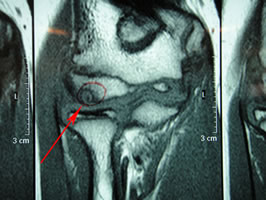

最後にMRI画像です。

T1強調画像(↓)

T2強調画像(↓)

T1・T2いずれも赤矢印先に丸くポツンと描出されているのが患部です。